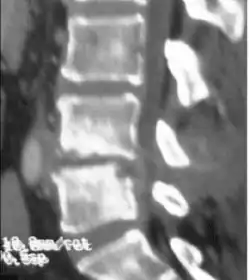

Discitis with anterior abscess (and disc space abscesses) -

An infected disc at the level of C5 C6 causing neurological symptoms